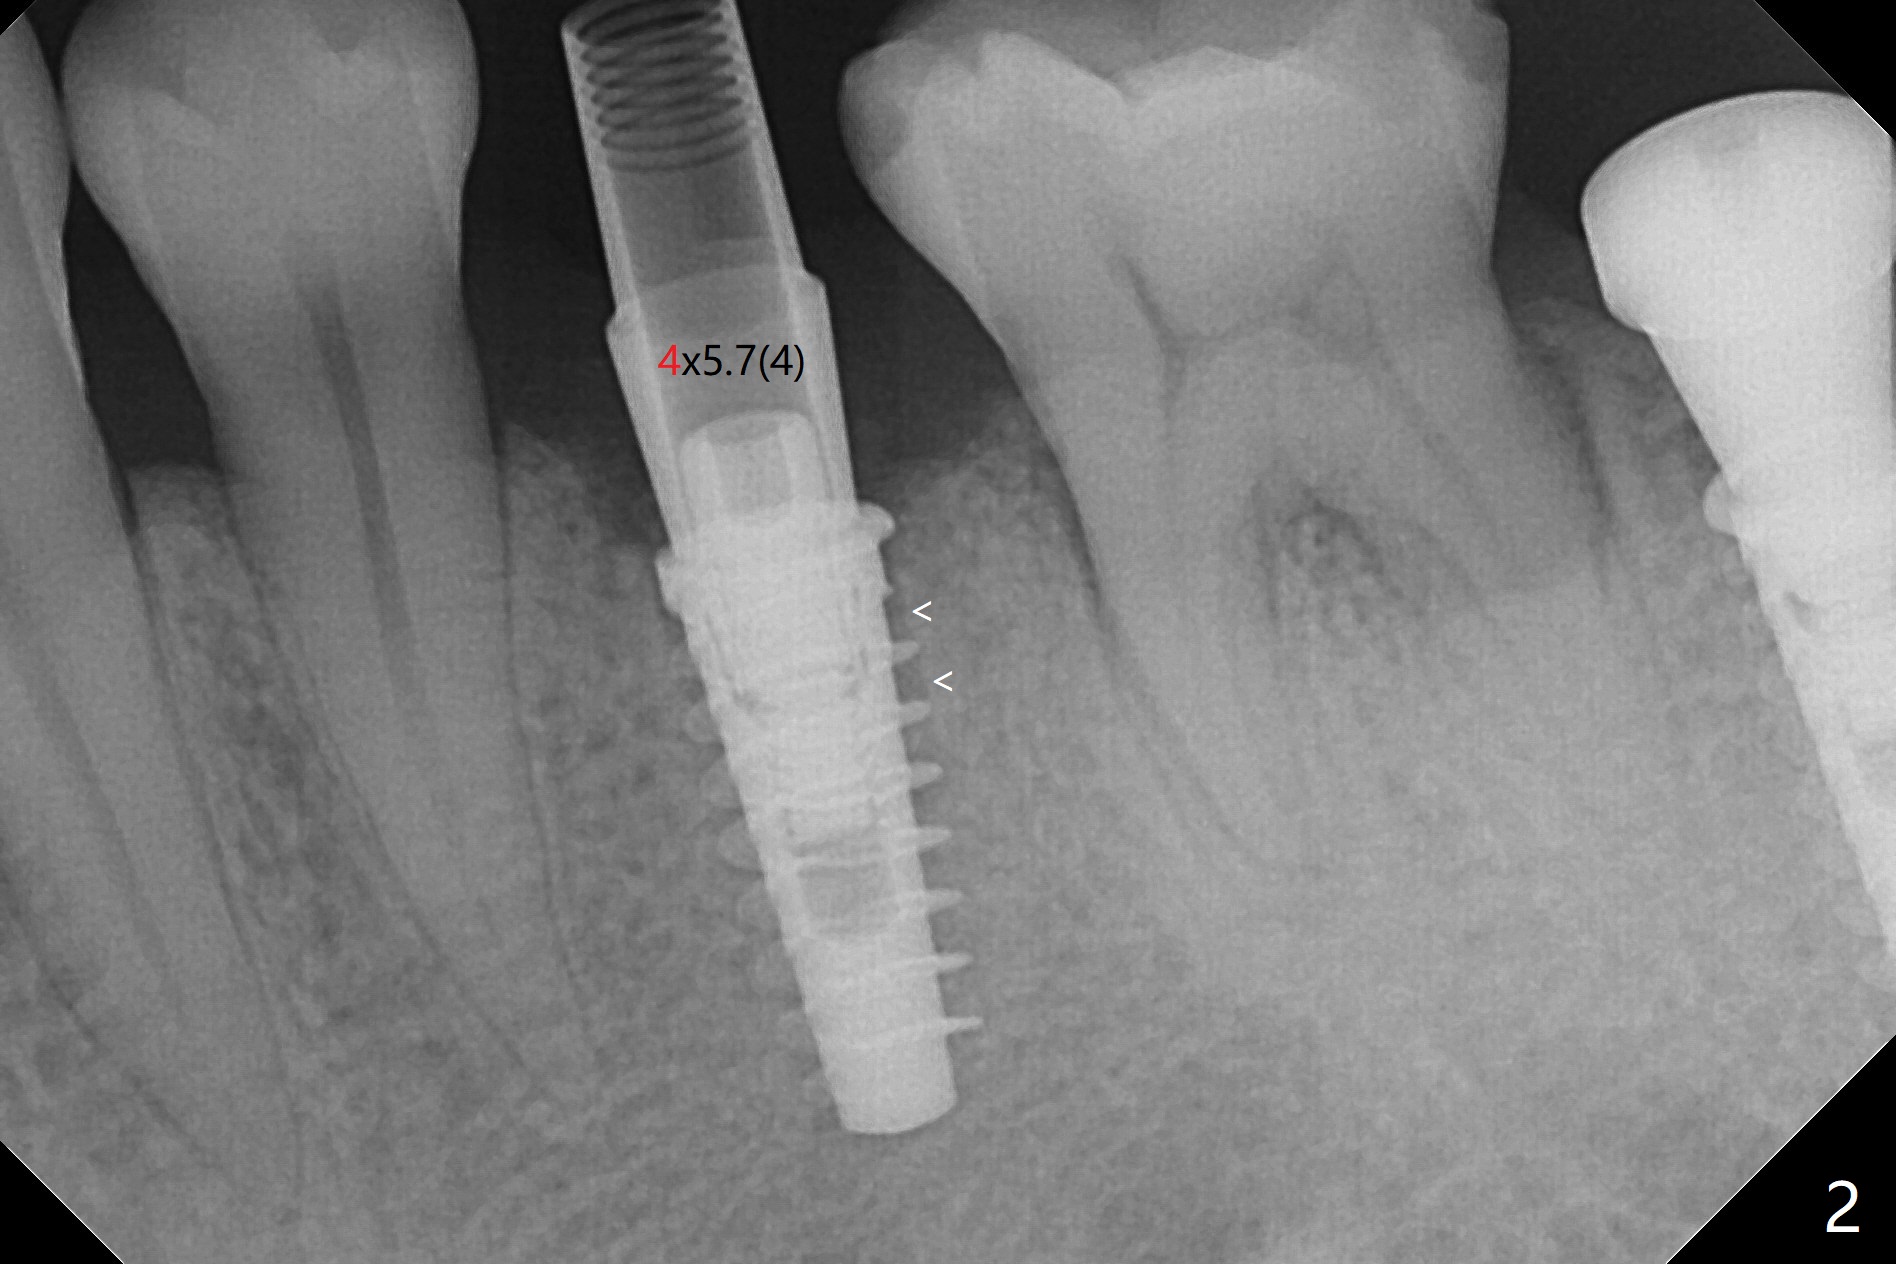

为了预防钻头遇到舌侧骨板而往颊侧偏移,有意不拔除第二前磨牙牙根。但是2.2毫米钻头钻洞很吃力,最后不得不拔除牙根,阻力骤然减少,顺利完成植入,而且颊侧间隙还够(图一,二),填入骨粉后远中螺纹间空间消失(图三箭头)。今后最后一个钻头完成钻洞后留在原位,周围放置适当量的骨粉,然后取出钻头,植入植体,这样空间可以比较全面充填。即刻种植没有颊侧偏移可能是因为设计时植体没有过多接触舌侧骨板(图四L)。第二磨牙延期种植需要切开是因为颊侧角化牙龈不足。术后两个月,前磨牙植体顶端似乎被牙槽嵴覆盖了(图五 *)。术后五个月,旋转7愈合基台,下面植体疼痛,可能与植体螺纹断裂有关(图六:>),5取模。